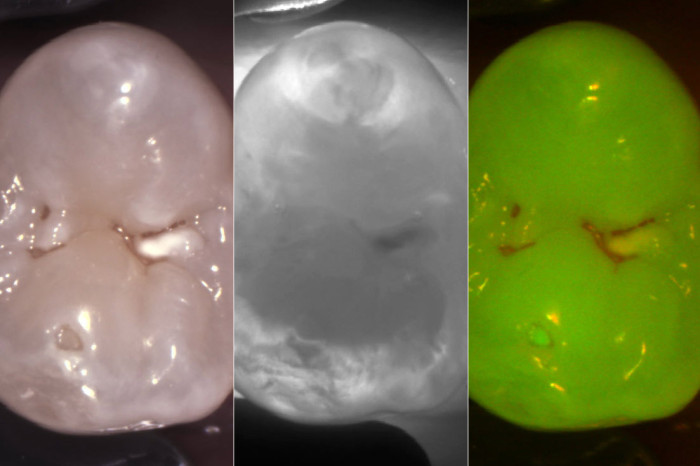

See more and show it all: Three diagnostic images instantly from one shot.

The KaVo DIAGNOcam Vision Full HD allows you to capture, present and save three relevant diagnostic images in less than one second. Seamlessly integrates into your current workflow while providing valuable information to both you and your patient.

You call it amazing - we call it the DIAGNOcam Vision Full HD.